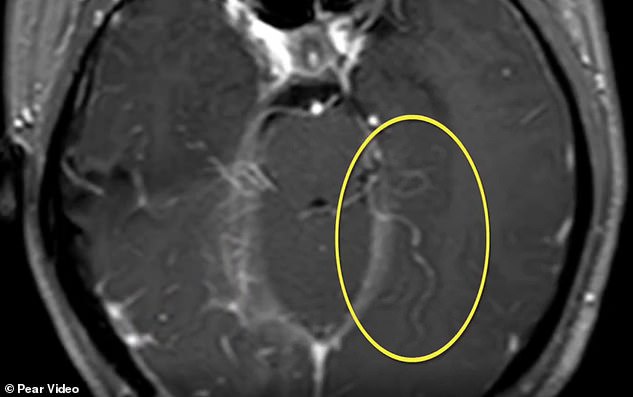

A live six-inch worm has been taken out from the brain of a 23-year-old Chinese woman who had suffered severe headaches. The CT scan shows the parasite in the patient's brain